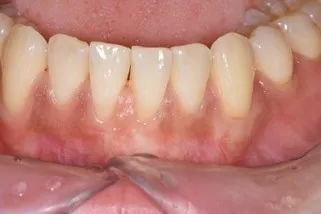

歯肉退縮の形成

治療名

根面被覆治療

治療回数・期間

1回(後日抜糸を行います)

副作用・リスク

歯肉が下がってしまったすべてを回復できるわけではなく、どの程度回復できるかは状態により異なります。

料金

¥110,000(税込)